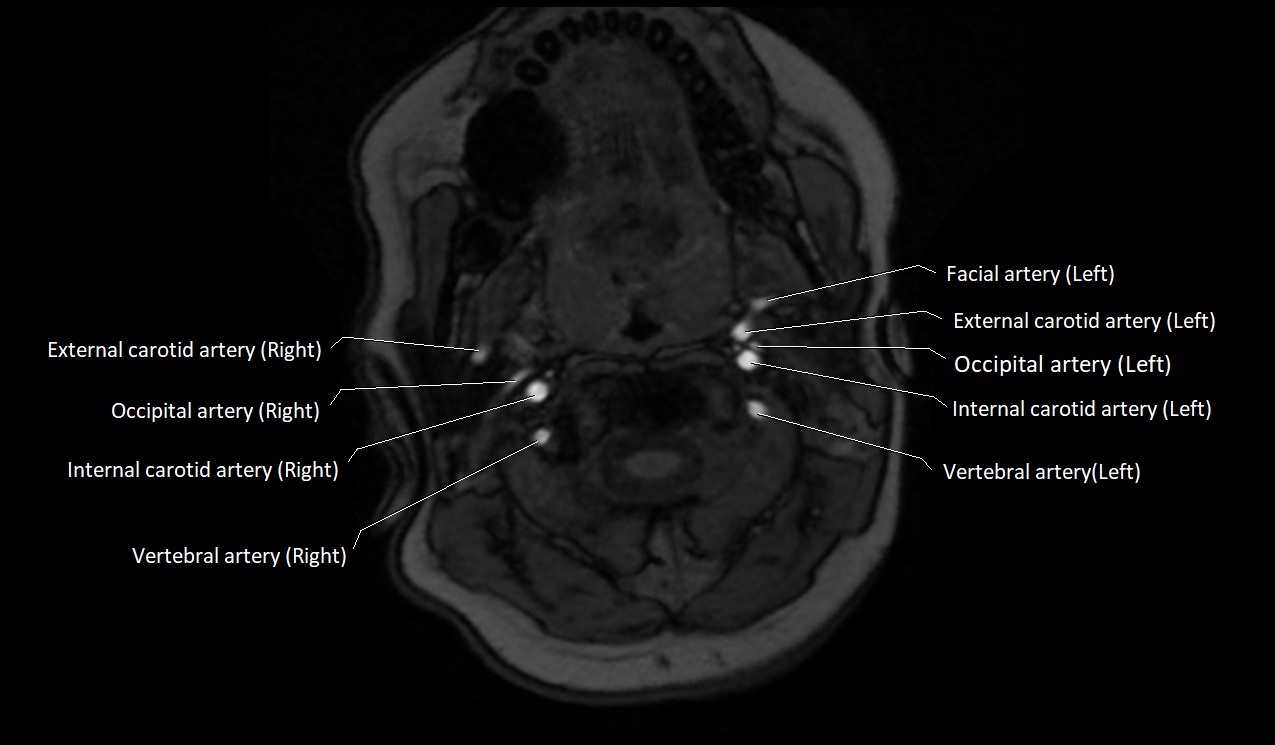

CT image

image